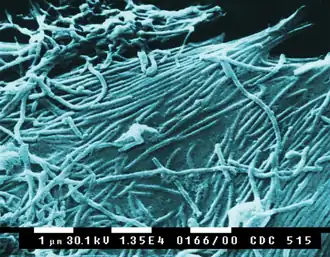

| Clockwise from top left: TEM of avian coronavirus, polio virus, bacteriophage Qβ, ebolavirus, tobacco mosaic virus, influenzavirus A, rotavirus, vesicular stomatitis virus. Center: phylogenetic tree of shared replication protein RdRp. | |

- Ebolavirus

Diseases caused by RNA viruses in Orthornavirae have been known throughout much of history, but their cause was only discovered in modern times. As a whole, RNA viruses were discovered during a time period of major advancements in molecular biology, including the discovery of mRNA as the immediate carrier of genetic information for protein synthesis.[34] Tobacco mosaic virus was discovered in 1898 and was the first virus to be discovered.[35] Viruses in the kingdom that are transmitted by arthropods have been a key target in the development of vector control, which often aims to prevent viral infections.[36] In modern history, numerous disease outbreaks have been caused by RdRp-encoding RNA viruses, including outbreaks caused by coronaviruses, ebola, and influenza.[37]